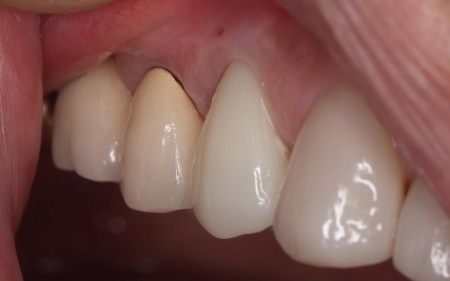

| 行ったご提案・治療内容 | 診断結果を丁寧に説明したうえで、古い被せ物を外し歯に合った新しい被せ物を作製する治療を提案し、同意いただきました。

この歯は過去の治療で被せ物を装着する際に歯の神経を取る根管治療を行っていました。 患者様は「見た目がきれいで長持ちする被せ物がいい」と希望され、被せ物の種類は自由診療のセラミックであるジルコニアクラウンを選択しています。 ジルコニアクラウンのメリット・デメリット まず古い被せ物を除去して土台の形を整え、精密な型取りを行いました。 |

治療後